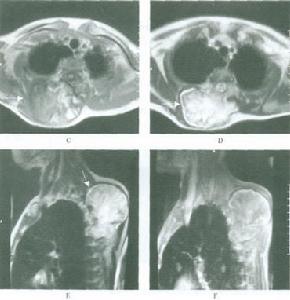

2.好發部位 骨膜軟骨瘤好發於長管狀骨特別是肱骨及股骨約占病例總數的70%。手、足部骨骼發病為25%骨膜軟骨瘤主要侵及乾骺端。典型的部位是肱、脛骨的近端及股骨的遠近端,常位於肌腱、韌帶的附著點處。

骨膜軟骨瘤應與骨膜軟骨肉瘤和骨皮質旁軟骨肉瘤相鑑別,但較困難。雖然骨膜軟骨肉瘤病人年齡常較骨膜軟骨瘤病人大,且腫瘤體積較大,但鶒在具體病例中難以區別。應參照X線表現等再具體考慮其診斷。